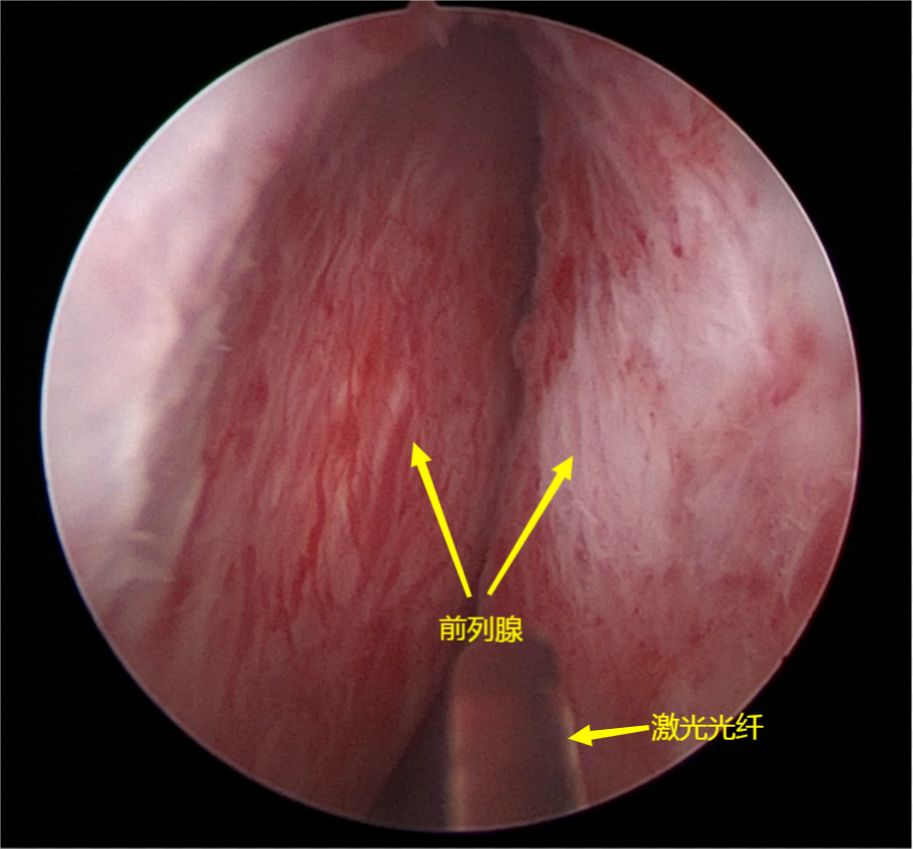

★前列腺增生微创剜除技术:以经尿道前列腺激光剜除术与等离子电切术为代表,技术国内先进。无需开刀,尤其钬激光/铥激光剜除术,具备出血少、恢复快的优势,多数患者术后1–2天即可出院,实现“日间手术”化诊疗。

科室配备瑞士EMS超声气压弹道混合动力碎石清石系统、美国科医人“双子星”激光、国产大功率钬激光、瑞柯恩优路铥激光系统,以及全套男科疾病工作站、尿动力学检测设备、结石成分分析系统等一流器械,为各类微创技术的开展提供了坚实保障。